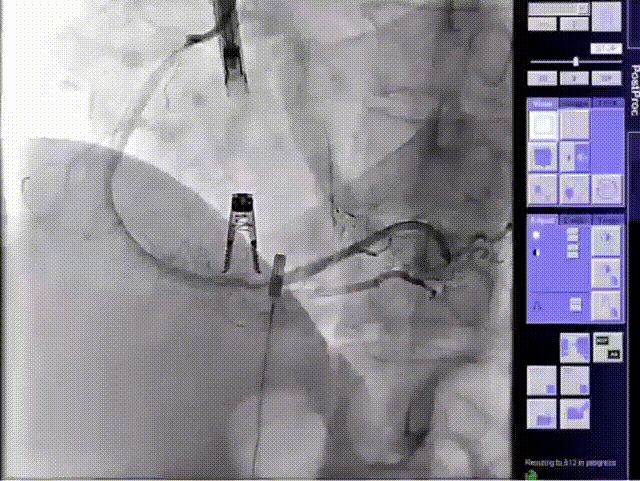

DSA

术前DSA

术后DSA